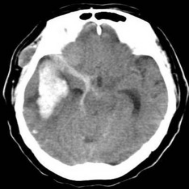

未破裂的脑动脉瘤的CT典型表现 破裂的脑动脉瘤 CT表现(SAH)